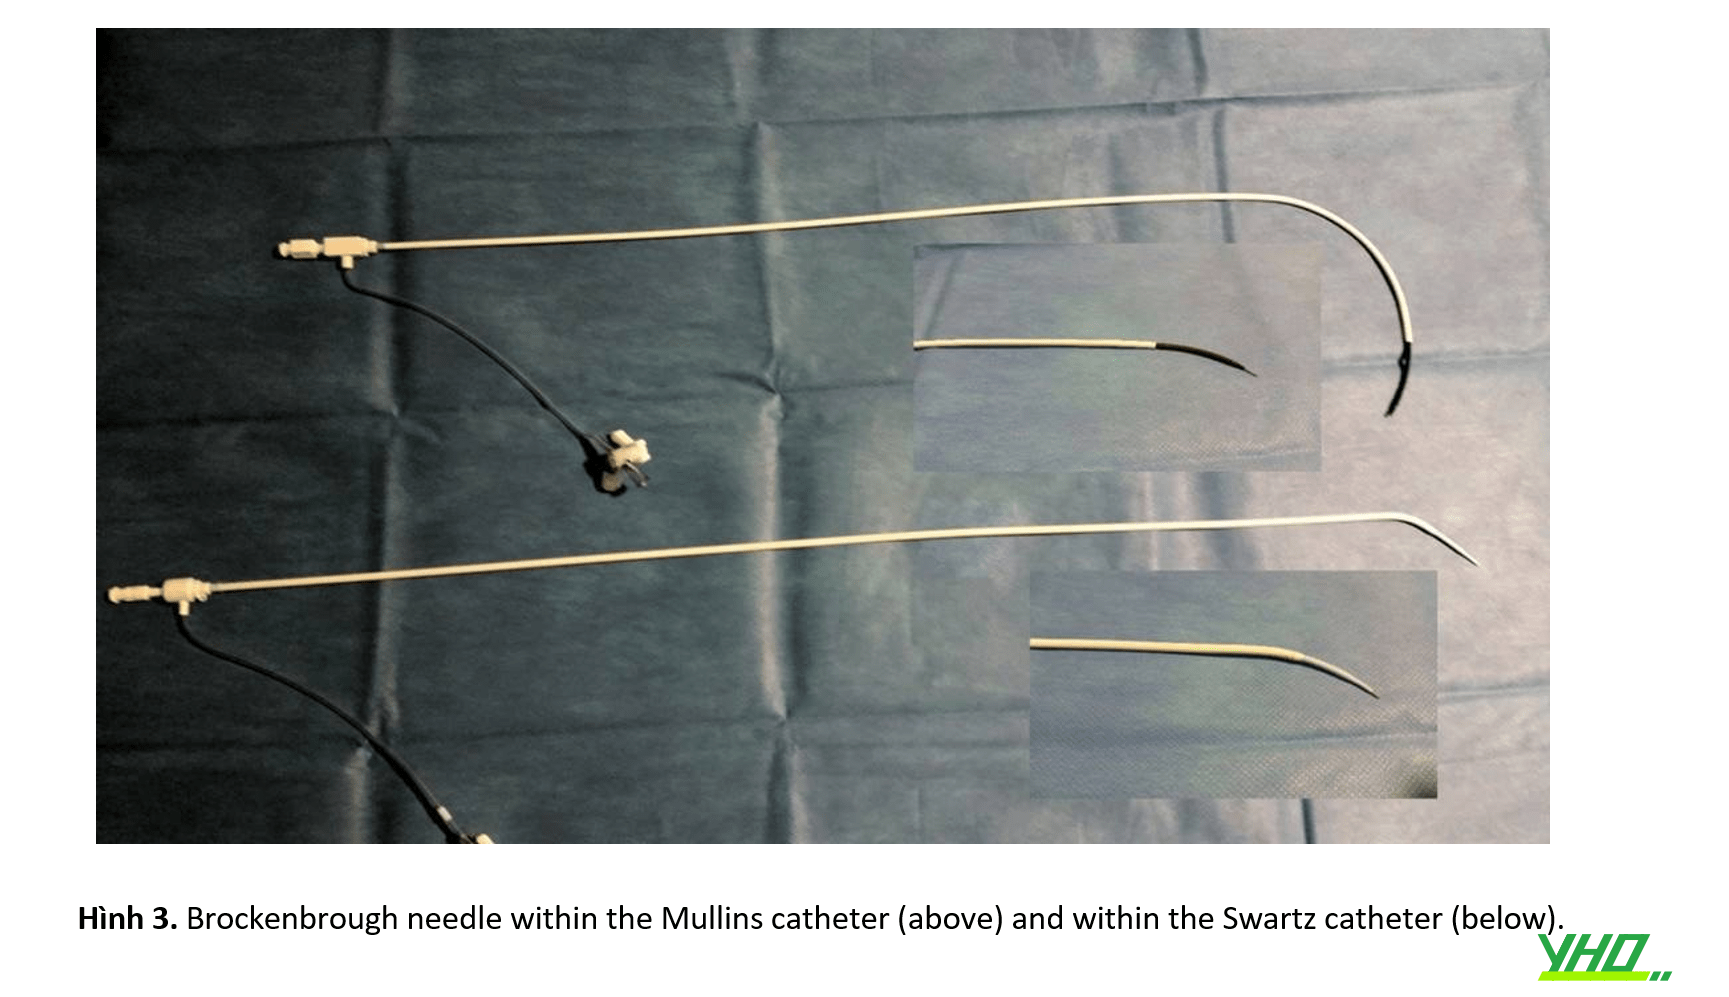

Các loại ống bao (sheath) gốc cong cố định thường được sử dụng: ống bao Mullins (Hình 2), ống thông Swartz (Hình 3).